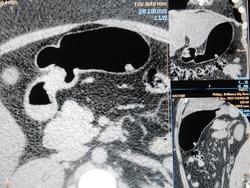

Больная В. 38 лет Диагноз: «Карциноид тела желудка малых размеров 11х9мм» (подтверждён гистологически).

1.-Пневмогастротопограмма

2.-Компьютерная пневмогастротомограмма

3.-2D -изображения с раздуванием желудка воздухом

4.-3D-реконструкция раздутого воздухом желудка (вид сзади)

5.-Виртуальная КТ-гастроскопия

6.- Гастроскопия. Фото представлены с разрешения доктора эндоскопического отделения ГБУЗ ЯО «ОКОБ» Д.В. Гусева.

Гастроскопия в режиме узкоспектральной эндоскопии (NBI)